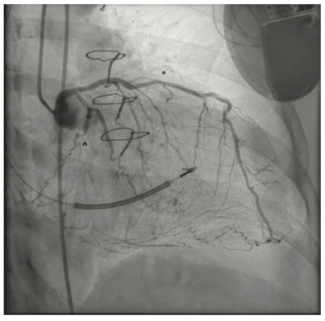

Pradnya Brijmohan Bhattad, MD; Luigi Pacifico, DO; Neeta M. Shah, MD

This is a 58-year-old female with a history of tuberous sclerosis. Transthoracic echocardiogram images demonstrated a heterogeneous mass in the mid right ventricle attached to the septum and the moderator band. The mass looked similar to what...